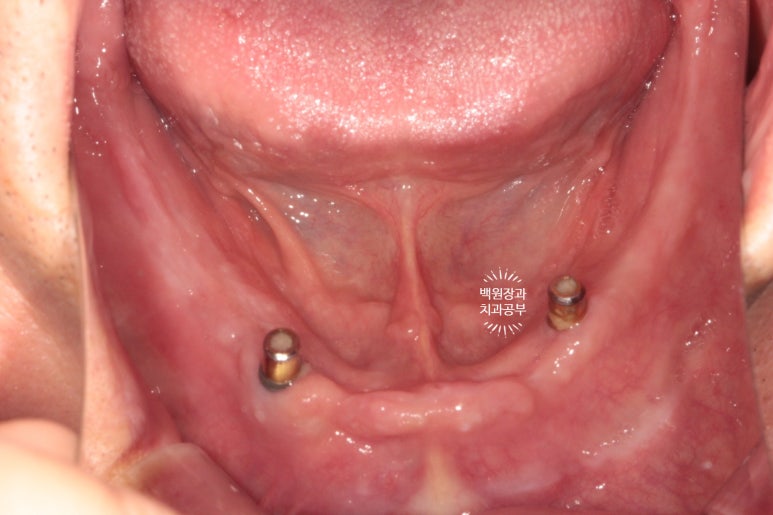

먼저 임플란트를 심어드린 아래턱 모습입니다.

두 개의 임플란트에 금색으로 된 모자를 연결해 주었어요.

이 부분이 나중에 임플란트와 연결할 단추 역할을 해줍니다.